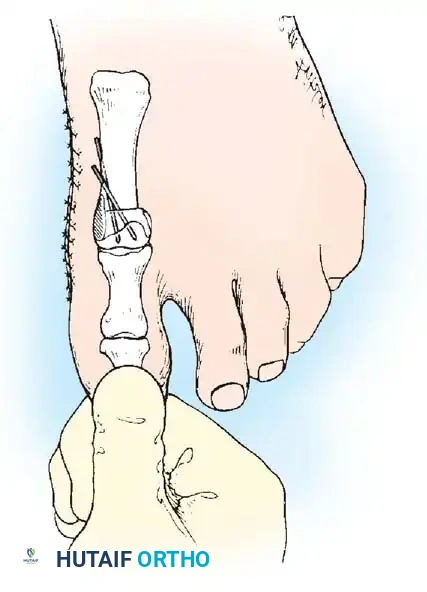

• Grasp the hallux in one hand and displace the proximal remnant medially so that, under direct vision, two longitudinal 0.062-inch Kirschner wires can be inserted.

• Hold the interphalangeal joint straight while drilling the wires from proximal to distal, emerging a few millimeters plantar to the nail plate.

• Return the foot to the corrected position, and drill the wires into the metatarsal head.

• While holding the metatarsal as far laterally as possible, cross the joint, and drive the wires out the plantar cortex just proximal to the head, while holding the hallux in 10 to 15 degrees of extension, neutral abduction, adduction, and rotation, and no translation dorsally or plantarward on the metatarsal head. The wires should penetrate only 2 to 3 mm past the cortex to avoid tenderness over the wires with weight bearing.

• If the Kirschner wires tend to “walk” on the rounded articular surface of the metatarsal head, use a small hemostat snugged up against the wire while it is being drilled to allow accurate placement. Proper placement of the wires and the desired position of the hallux on the metatarsal may require several attempts. The medial aspect of the proximal phalanx should not rest medial to the medial aspect of the metatarsal head.

• Place the hallux in the neutral medial-lateral plane and in 10 degrees of extension.

• Before the second wire is driven into the fi rst metatarsal head, place the hallux in proper rotation, using the plane of the nail as a guide. The initial length of the hallux is maintained by the wires. Later, collapse occurs when the wires are removed, but improved encapsulation of the hemiarthroplasty, by maintaining length for the fi rst few weeks, may help maintain a more desirable position long-term.

• Cut the wires off 2 to 3 mm distal to the skin edge.

• When the sesamoid has been removed, insert two 0.062-inch Kirschner wires retrograde from the tip of the toe 2 to 3 mm plantar to the nail bed, leaving about 5 to 7 mm of the pins exposed at the base of the phalangeal remnant to help align the phalanx on the metatarsal before antegrade passage of the pins into the metatarsal (Fig. 78-31F).

• While standing next to the patient looking distally at the dorsum of the foot, dorsifl ex the ankle to neutral.

• Viewing the foot as the patient would, hold the fi rst metatarsal fi rmly, and move its distal end laterally. Hold this position with one hand, and use the other hand to place the hallux on the metatarsal head and out to length.

• While holding the fi rst ray straight with the foot vertical, have an assistant insert the wires from distal to proximal (Fig. 78-31G). Often these wires, which run through the fi rst metatarsal and hallux, hold the fi rst ray straight, and most of this correction is maintained after the wires have been removed.

• Close the capsule with a purse-string suture as previously described in the original technique (Fig. 78-31H to J).